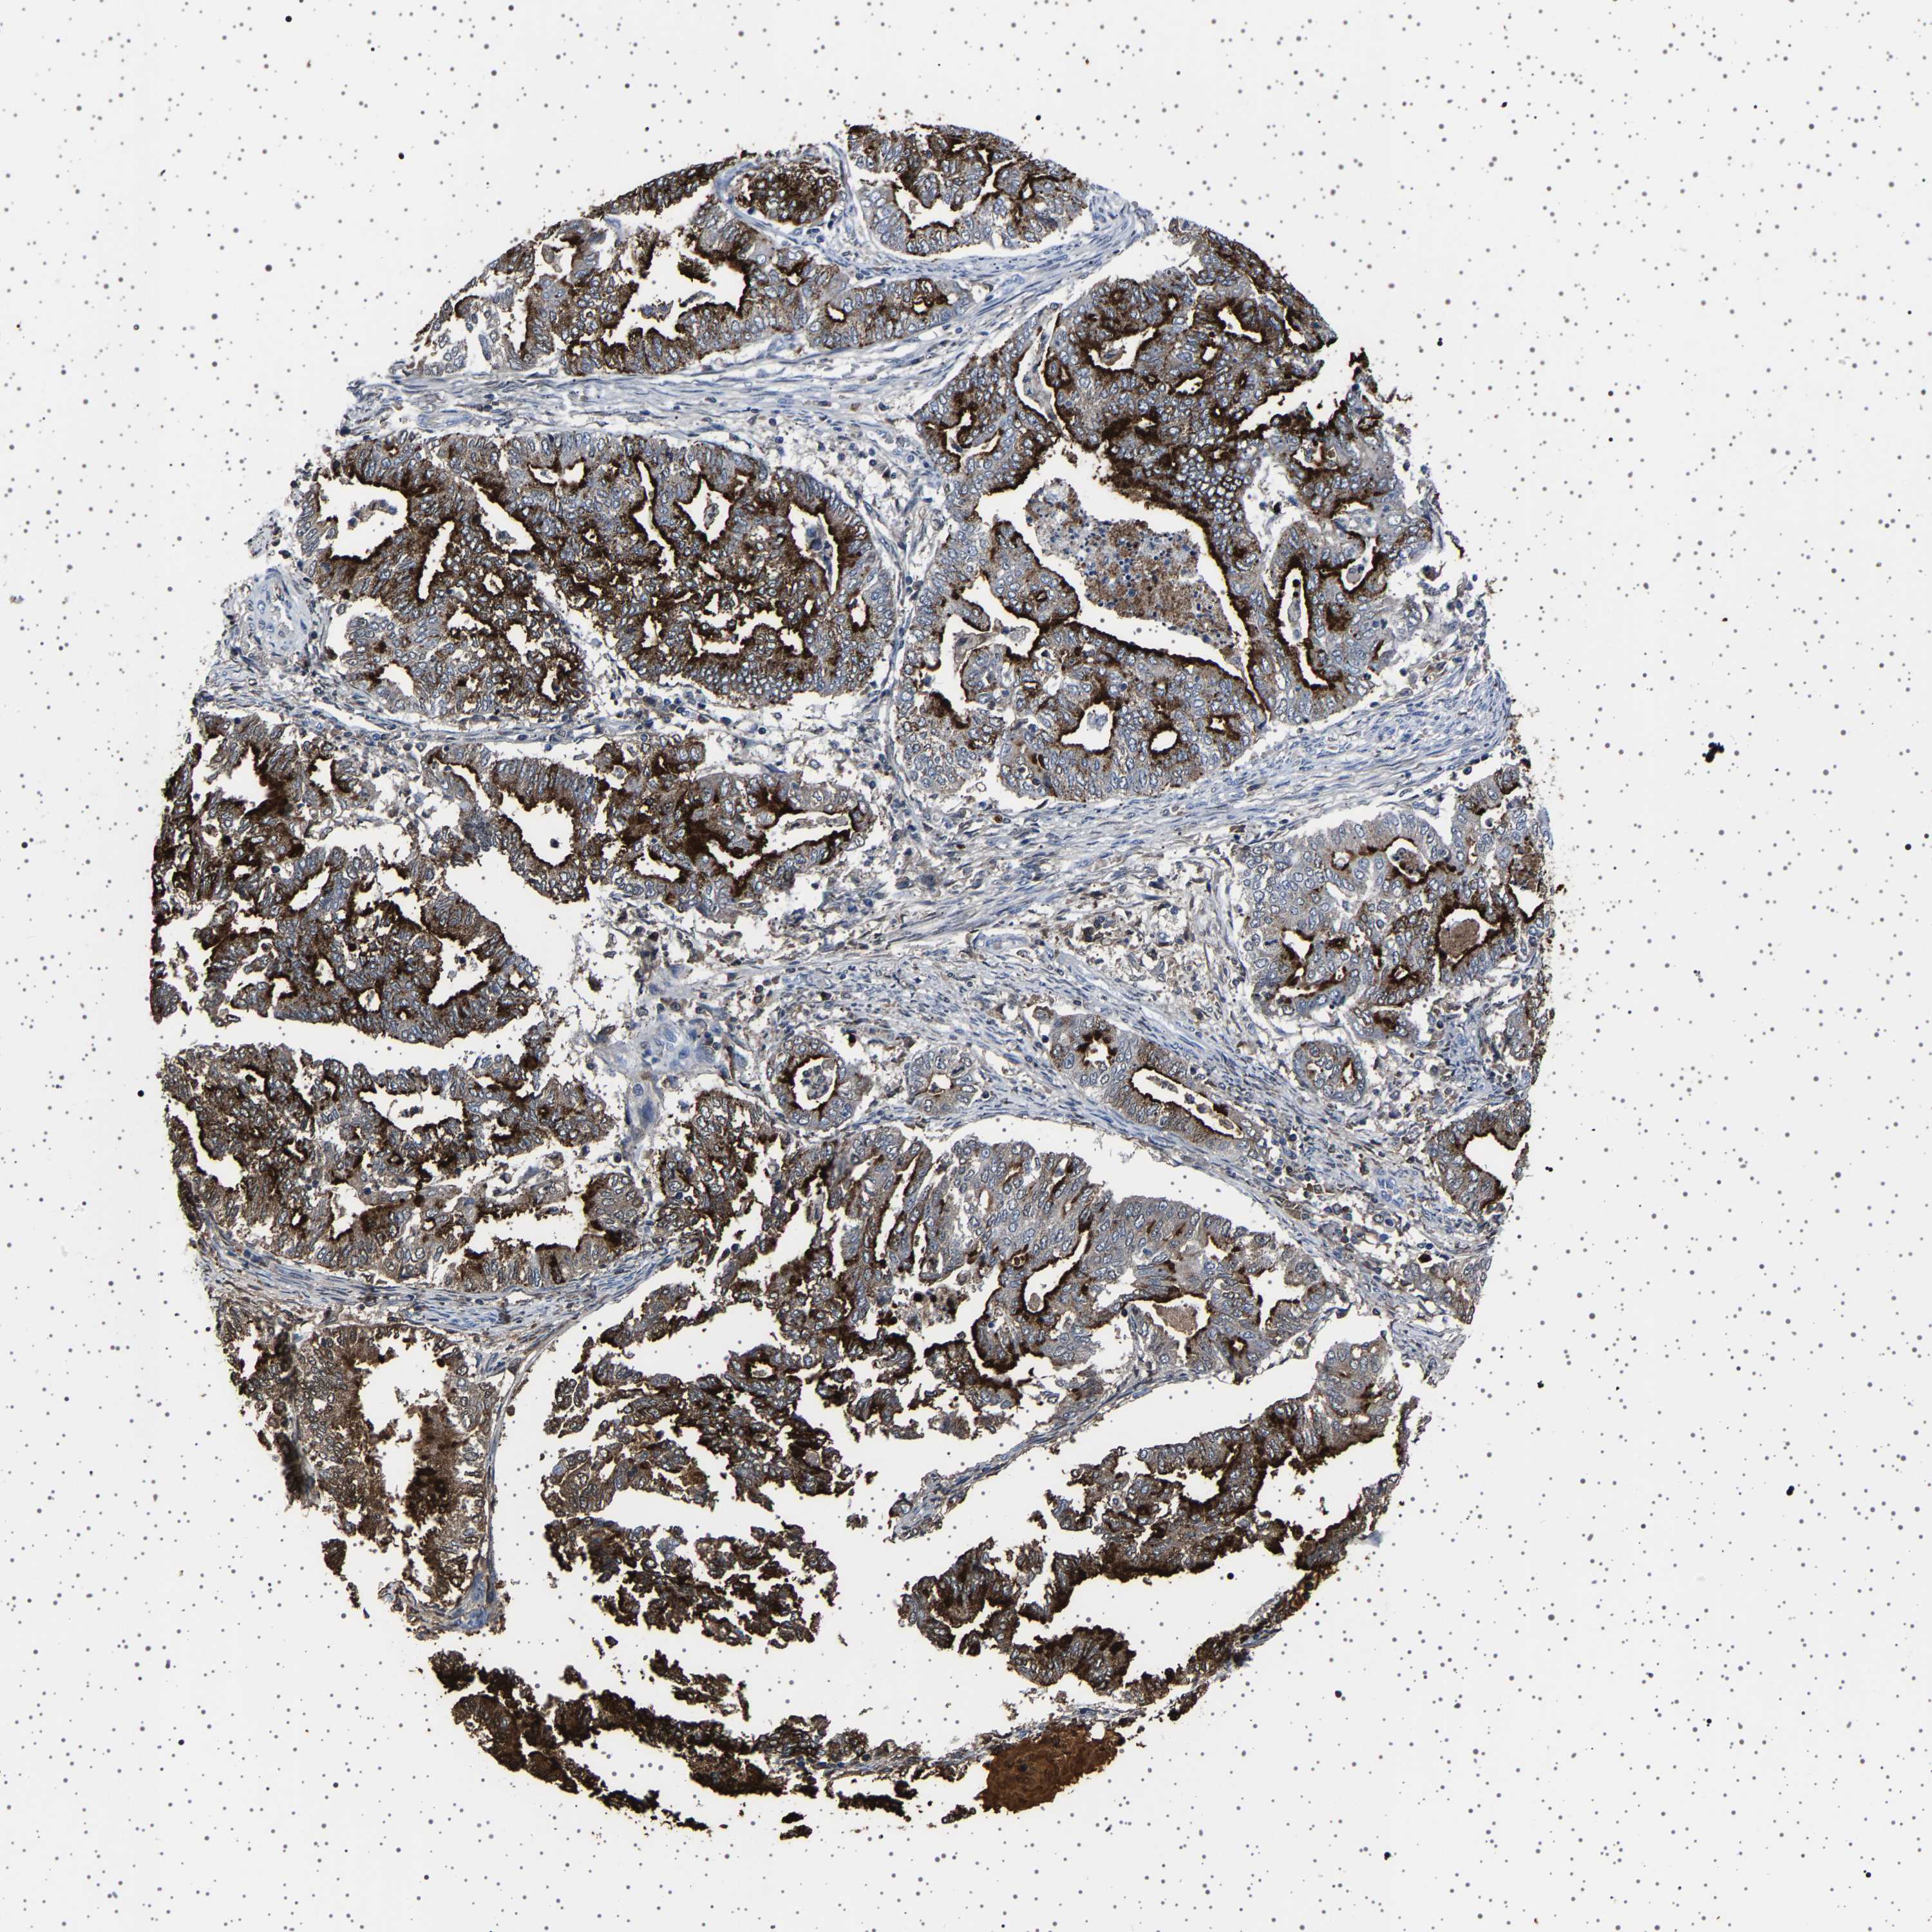

ENDOMETRIAL CANCER - Protein expressioni

A mouse-over function shows sample information and annotation data. Click on an image to view it in a full screen mode. Samples can be filtered based on level of antibody staining by selecting one or several of the following categories: high, medium, low and not detected. The assay and annotation is described here.

Note that samples used for immunohistochemistry by the Human Protein Atlas do not correspond to samples in the TCGA dataset.

Antibody stainingi

Antibody staining in the annotated cell types in the current human tissue is reported as not detected, low, medium, or high, based on conventional immunohistochemistry profiling in selected tissues. This score is based on the combination of the staining intensity and fraction of stained cells.

Each image is clickable and will lead to virtual microscopy that enables deeper exploration of all samples and also displays staining intensity scores, fraction scores and subcellular localization as well as patient and tissue information for each sample.

Antibody HPA035464

Antibody CAB020681

Staining

High

Medium

Low

Not detected

Intensity

Strong

Moderate

Weak

Negative

Quantity

>75%

75%-25%

<25%

None

Location

Nuclear

Cytoplasmic/membranous

Cytoplasmic/membranous,nuclear

Adenocarcinoma, NOS